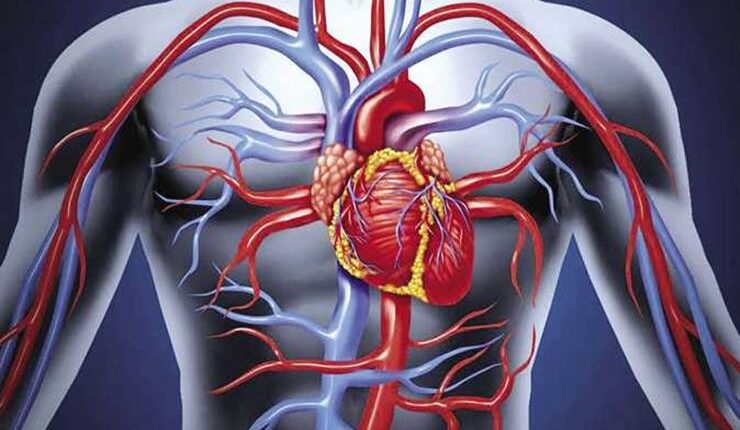

مع حلول أول أيام رمضان، يدخل الجسم في مرحلة انتقالية مفاجئة من نظام غذائي معتاد إلى نمط صيام يمتد لساعات طويلة. هذا التغيير لا يمرّ بهدوء دائماً، بل تصاحبه تحولات فسيولوجية واضحة قد تفسّر الشعور بالتعب أو الصداع أو تقلب المزاج.

خلال أول 6 إلى 8 ساعات من الصيام، يعتمد الجسم على مخزون الغلوكوز الموجود في الدم والكبد. وبعد نفاد هذا المخزون تدريجياً، يبدأ في البحث عن مصادر بديلة للطاقة.

مع استمرار الصيام، يبدأ الجسم في تكسير جزء من الدهون لإنتاج الطاقة. هذه العملية طبيعية وتُعد من آليات التكيف الذكية، لكنها قد تكون مصحوبة بشعور بالإرهاق في اليومين الأولين، إلى أن يتأقلم الجسم.